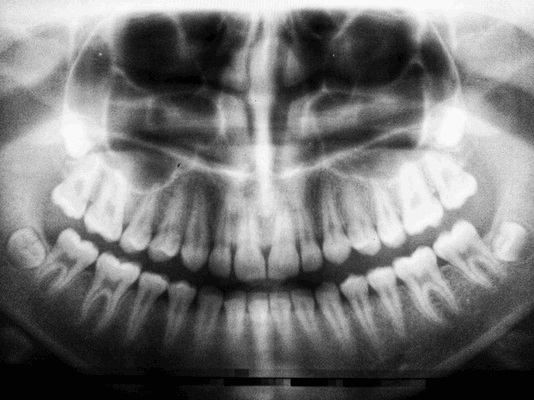

Обычно врач-ортопед-стоматолог перед протезированием рекомендует сделать обзорный снимок всех зубов, такой снимок называется - ортопантомограмма (ОПТГ). Чтобы в целом оценить состояние зубов, костной ткани, выявить те проблемы, которые могут пациента и не беспокоить, но всё же являются серьезными и требуют решения.

Проводится с целью выявить состояние костной ткани и зубных корней, исключить противопоказания. Если вы лечите один зуб, будет достаточно прицельного снимка (рентген). Если врачу необходимо увидеть картину целиком, нужен обзорный снимок (ортопантомограмма). Перед имплантацией вас направят на компьютерную томографию.

Панорамный снимок, КТ. Позволяют увидеть состояние челюстной системы, костной ткани, нервов, носовых пазух. На основании этого врач расписывает план лечения.

Обычно врач-ортопед-стоматолог перед протезированием рекомендует сделать обзорный снимок всех зубов, такой снимок называется - ортопантомограмма (ОПТГ). Чтобы в целом оценить состояние зубов, костной ткани, выявить те проблемы, которые могут пациента и не беспокоить, но всё же являются серьезными и требуют решения. Затем после тщательного обследования составляется индивидуальный план подготовки к протезированию.